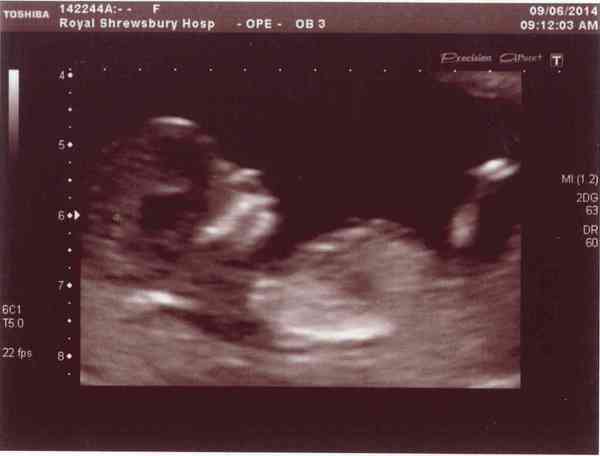

Scan was today. I'm feeling like a weight has been lifted. Baby all present and correct, everything looked fine. It was a proper little wiggler, bouncing all over the place, waving and sucking its thumb. Was lovely to see. Sonographer said the head looked well formed, so risk of Spina Bifida should be low - I've been worried about that because I really haven't been taking my folic acid very often. EDD has come forward by 4 days, which I wasn't expecting, as we only DTD twice and I'm pretty sure of when I ovulated, based on dates etc. Conception bloody well confuses me! Grin